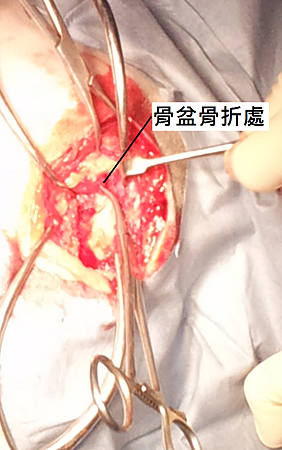

小可每天最喜歡的事情就是跟阿嬤上街買菜,有一天在滿載而歸的路途上,小可看到旁邊機車上有一位帥氣的大黃金獵犬,想過去交朋友,但小可忘了自己還在機車上。於是,小可摔落地面被後方了機車壓過去。阿嬤非常緊張,小可也嚇呆了,趕緊送到我們醫院進行檢查,當時小可已經無法走路只能坐著,但還是十分的親人撒嬌令人十分捨不得,經過X光攝影之後確診左右雙側骨盆骨折與左腳大腿骨靠近膝關節處骨折。

上圖,骨盆骨折處。

小動物骨盆骨折大多見於車禍、跳樓的毛孩子,如果不做適當的外科處理毛孩子往往會無法走路,並且因為破裂的骨盆向內壓迫骨盆腔導致無法排便。骨盆骨折是需要特別注意的,因為骨折碎片有可能會將尿道、神經割斷,斷裂太久的骨盆會與骨盆腔組織沾連而無法復位,所以發現有骨盆骨折的毛寶貝應該盡速就醫,觀察生命情況,並且盡速處理。